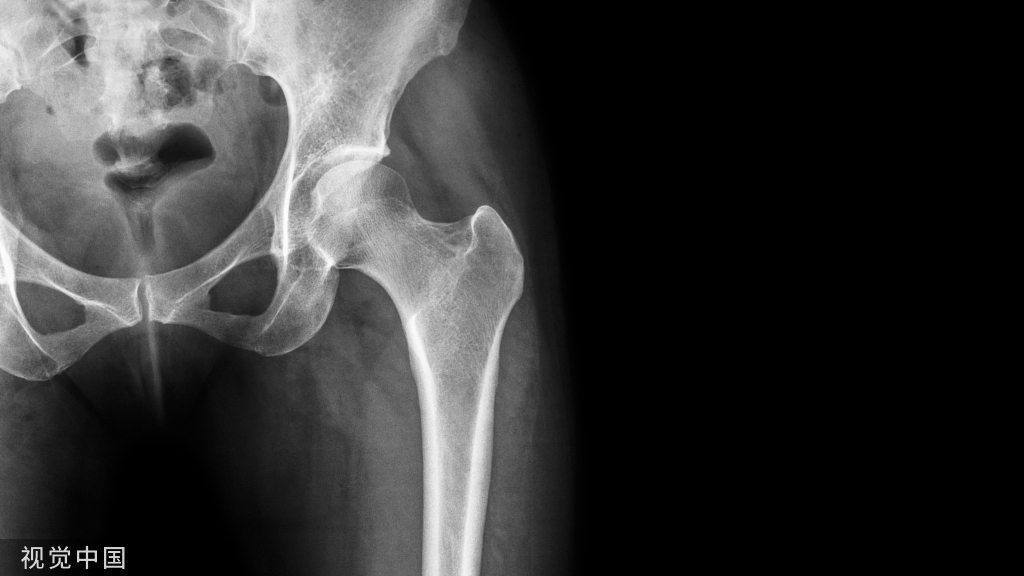

由于炎症反应,羟基磷灰石晶体的沉积可能会引起剧烈的疼痛。在急性期,肌腱及其周围可见严重的水肿症。X线片有助于诊断钙化性肌腱炎或滑囊炎,因为钙化沉积在mr图像上很容易被忽略。